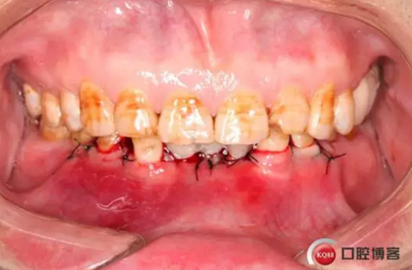

治療方法 針對下頜深覆頜及骨量情況,給患者提供方案:第一步通過34、33、43、44冠延長,改善前牙深覆頜及咬合空間不足。第二步因骨量寬度不足,無法行常規(guī)種植,建議在32、42種植3.0直徑的MINI型種植體并同期臨時修復改善美觀。

下圖是術后照片 治療過程 術前測量上下牙長度比例,確定水激光冠延長深度約3mm,拔除31、41,在術區(qū)減低牙槽嵴高度,32、42位點種植MINI型一段式種植體,使用臨時愈合帽行暫時性修復。